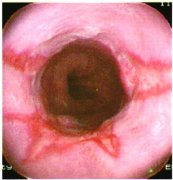

食管炎即食道炎,泛指食管黏膜浅层或深层组织由于受到刺激或损伤,食管黏膜发生水肿和充血而引发的炎症。化学性刺激包括胃酸、胆汁、烈酒以及强酸、强碱、药物等;物理性刺激包括烫的食物、食管异物(鱼刺等)嵌顿,长期放置鼻胃管等。由于化学治疗、放射治疗导致食管局部受损,或患者本身抵抗力下降导致结核杆菌、真菌(念珠菌)或病毒感染亦可引发食管炎。临床最常见的是胃酸反流引起的反流性食管炎。